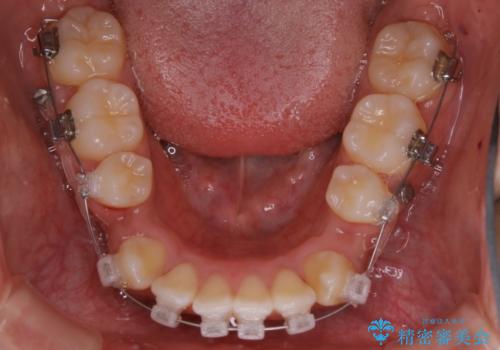

- 矯正装置

- クリア装置

親知らずと、前から4番目の歯を抜歯してワイヤー装置による矯正治療を行いました。

人前に出ることが多いため、当初は目立たない装置をご希望されていましたが、歯の移動距離が大きいため効率よく歯を動かせる表側の装置での治療をお勧めしました。すれ違ってしまっていた奥歯もしっかり治すことができました。